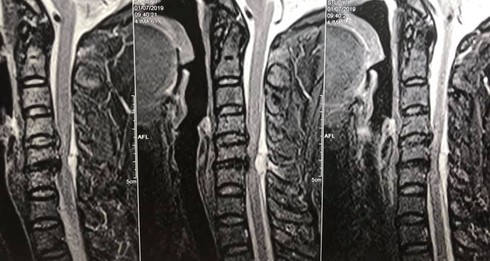

Hình ảnh tổn thương của bệnh nhân qua phim chụp. |

Bác sĩ Khánh cho biết, kết quả chụp cộng hưởng từ cho thấy bệnh nhân có một khối máu tụ rất to đang chèn ép nặng cột sống cổ, đó chính là nguyên nhân gây liệt hai chân. Bác sĩ đã phải mổ cấp cứu ngay trong đêm, để lấy phần máu tụ ở đốt sống cổ.